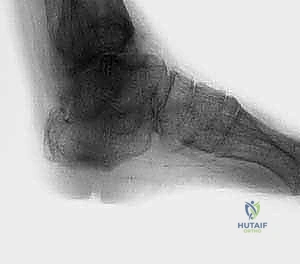

2. التصوير الطبي المتقدم

- الأشعة السينية (X-rays) أثناء الوقوف: وهي الخطوة الأهم لرؤية العظام تحت تأثير وزن الجسم. تظهر الأشعة اختفاء المسافة المفصلية، وتكوّن النتوءات العظمية، ودرجة التشوه المحوري.

- الأشعة المقطعية (CT Scan): ضرورية جداً لتقييم جودة العظام بشكل ثلاثي الأبعاد، وتحديد مدى التجاويف العظمية (Cysts) التي قد تحتاج إلى ترقيع عظمي أثناء الجراحة.

في الحالات المرضية المتقدمة التي يستهدفها هذا المقال، يكون التلف قد طال كلا المفصلين. الألم لا يأتي فقط من حركة القدم لأعلى ولأسفل، بل أيضاً من أي محاولة للتكيف مع الأرض. الغضاريف التي كانت تعمل كوسائد ملساء قد اختفت تماماً، والعظام قد تشوهت، وتكونت نتوءات عظمية (Osteophytes) تزيد من تقييد الحركة وتضاعف الألم.

- تشوه مرئي في القدم: يلاحظ المريض أو الطبيب انحرافاً واضحاً في القدم. قد تميل القدم بشدة إلى الداخل (Varus) أو إلى الخارج (Valgus). هذا التشوه يجعل من المستحيل ارتداء الأحذية العادية.

الخطوة الثالثة: تصحيح التشوه وإعادة المحاذاة

يتم وضع القدم في الوضعية المثالية للمشي: زاوية 90 درجة مع الساق (Neutral Dorsiflexion)، مع ميل طفيف جداً للخارج (Valgus) بحوالي 5 درجات. هذا الوضع الدقيق هو الذي سيسمح للمريض بالمشي بشكل طبيعي بعد الجراحة دون العرج. يتم تثبيت العظام مؤقتاً بأسلاك معدنية (K-wires) ويتم التأكد من الوضعية باستخدام جهاز الأشعة السينية داخل غرفة العمليات (Fluoroscopy).